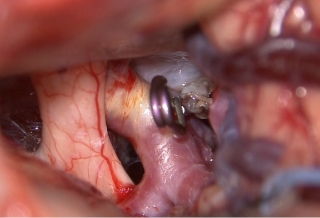

治療前

治療後

物が二重に見えるようになって発症した内頚動脈大型動脈瘤(矢印)の症例です。クリッピング術で直接動脈瘤をつぶすことができないため、バイパス術(矢印)を増設し内頚動脈を遮断することで動脈瘤を治療しました。